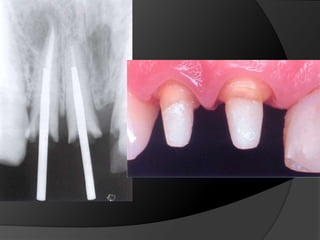

Diagnóstico y Planificación MultidisciplinariaEl examen clínico y la historia clínica nos darán información sobre los factores locales y sistémicos que pueden tener gran influencia en la obtención de un pronóstico para el tratamiento propuesto

Diagnóstico y Planificación MultidisciplinariaHistoria ClínicaAnamnesisFotografía clínica Montaje modelos de estudioEncerados DiagnósticosEvaluación Radiográfica Radiografías PeriapicalesRadiografía PanorámicaEvaluación DentalEvaluación PeriodontalEvaluación EndodónticaEvaluación OclusalEvaluación Articular?

Diagnóstico y PlanificaciónMultidisciplinariaEl examen clínico y la historia clínica nos darán información sobre los factores locales y sistémicos que pueden tener gran influencia en la obtención de un pronóstico para el tratamiento propuesto

Diagnóstico y PlanificaciónMultidisciplinariaHistoria ClínicaAnamnesisFotografía clínica Montaje modelos de estudioEncerados DiagnósticosEvaluación Radiográfica Radiografías PeriapicalesRadiografía PanorámicaEvaluación DentalEvaluación PeriodontalEvaluación EndodónticaEvaluación OclusalEvaluación Articular?